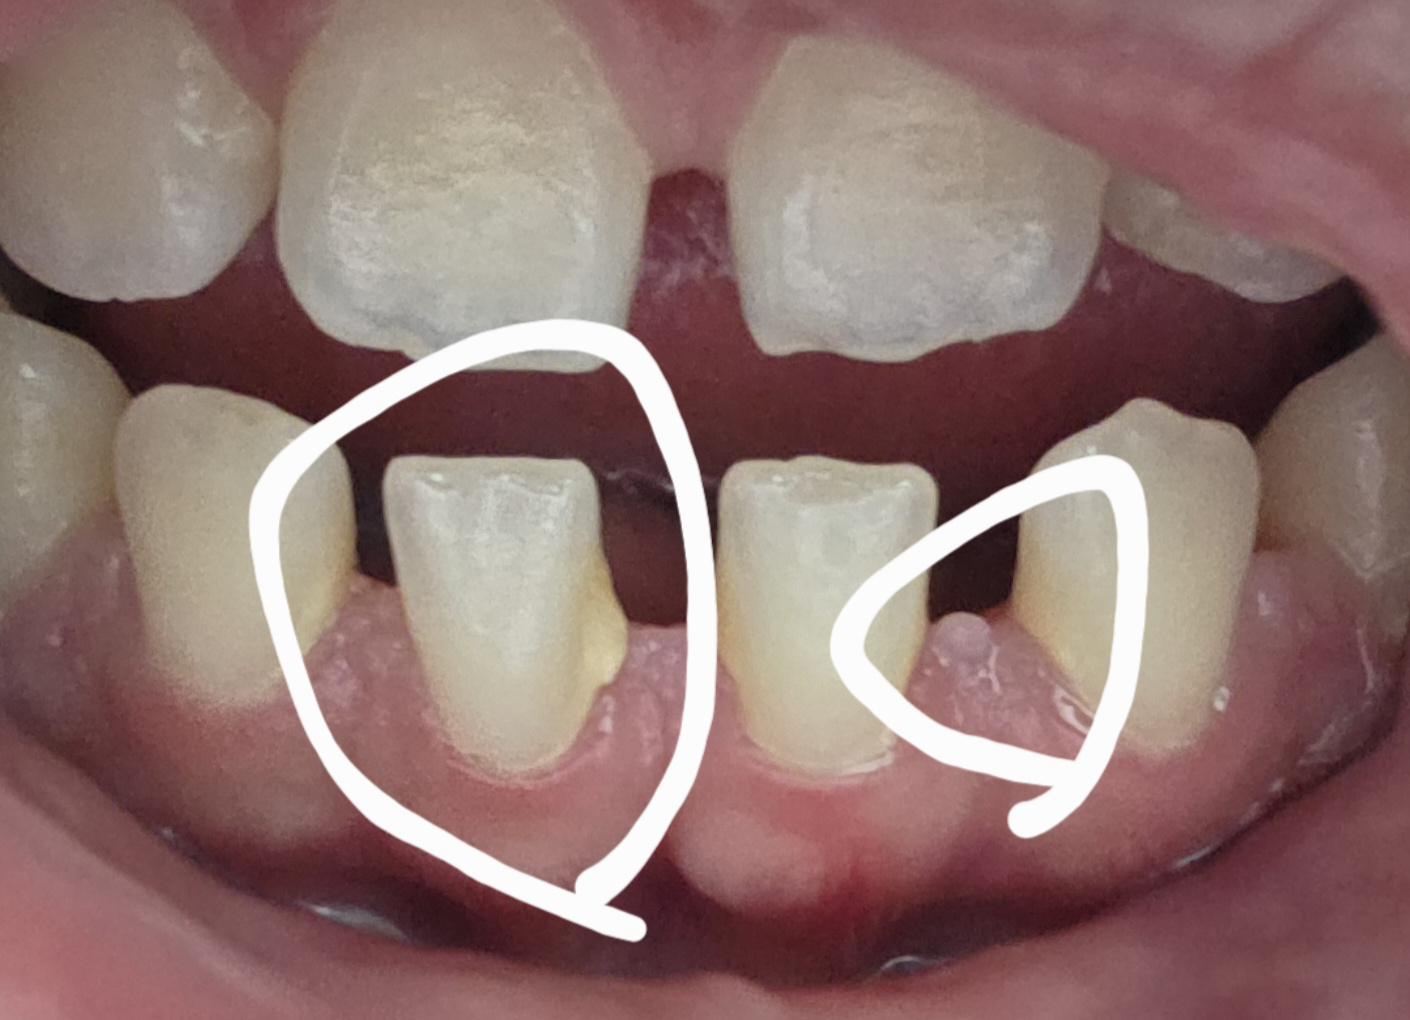

이거 혹시 치석인가요? 궁금합니다..

첫번째 하얀색원에 앞니 오른쪽 노란색 살짝 붙어있능게 치석맞나요? 치석이 맞다면 당장 제거할정도로 위험한건지 궁금합니다!

• 1번 째 사진

1. 네 치석 맞습니다 스케일링해주세요

사진상으로 왼쪽에 보이는것은 치석이 맞으며 오른쪽에 보이는것은 치석이라기 보다 치아 조직으로 보입니다.